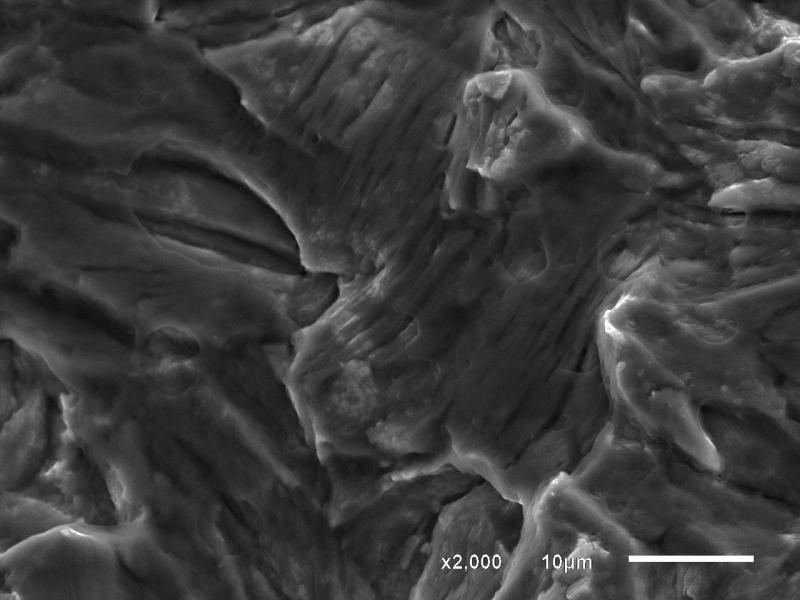

纯钛接骨板断口分析

是纯Ti金属接骨板,在人体内使用6个月后断裂。最后一张图是否为疲劳台阶,我推测为疲劳腐蚀断裂,本人刚开始接触断口,请各位帮忙一起分析断口。

裂源

台阶是什么??

钛和钛合金板断裂大部分是由于本身存在裂纹源,很多时候是我们没有注意到得地方出现了,特别是孔德位置